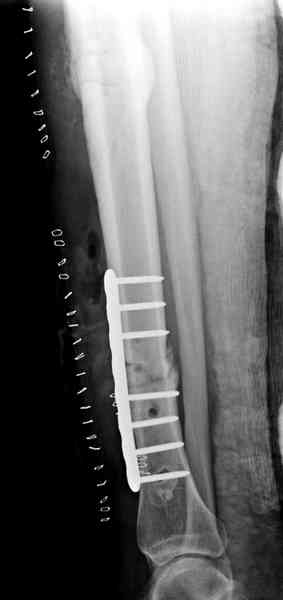

Недавно на нашей ежемесячной Morbidity&Mortality

conference мы разбирали похожий случай, ложный сустав большеберцовой кости после резекции опухоли.

К нашему онкологу-ортопеду обратился больной с жалобами на боли в голени, из рассказа - год назад была сделана биопсия большеберцовой кости, но название заболевания "не запомнил”.

Оперирован в военном госпитале с заменой сегмента

аллокостью большеберцовой кости и после демобилизации явился для постоянного наблюдения по месту жительства.

Наши имели проблему со сращением, пришлось им сделать динамизацию, дополнительную аутопластику.

Снимки представлены.